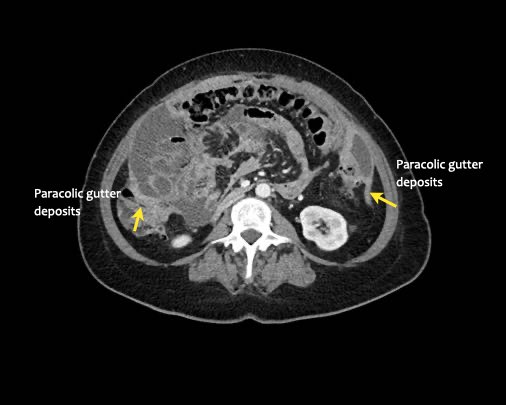

Đôi khi có thể thấy di căn khối u lan ra phía trước bàng quang, nhưng không xâm lấn thành bàng quang, do bàng quang là cơ quan nằm ngoài phúc mạc.

Tuy nhiên, vòm bàng quang phía trên và ống niệu rốn được ngăn cách với khoang bụng bởi một lớp phúc mạc thành, tạo thành đích tiềm năng cho các tế bào khối u.

Đặc biệt khi bàng quang đầy, các tổn thương di căn phúc mạc có thể được quan sát thấy ở phía trước bàng quang, áp sát thành bụng trước.

Đây không phải là bệnh lý quanh bàng quang, vì khoang quanh bàng quang nằm ngoài phúc mạc và không thông với khoang trong phúc mạc.